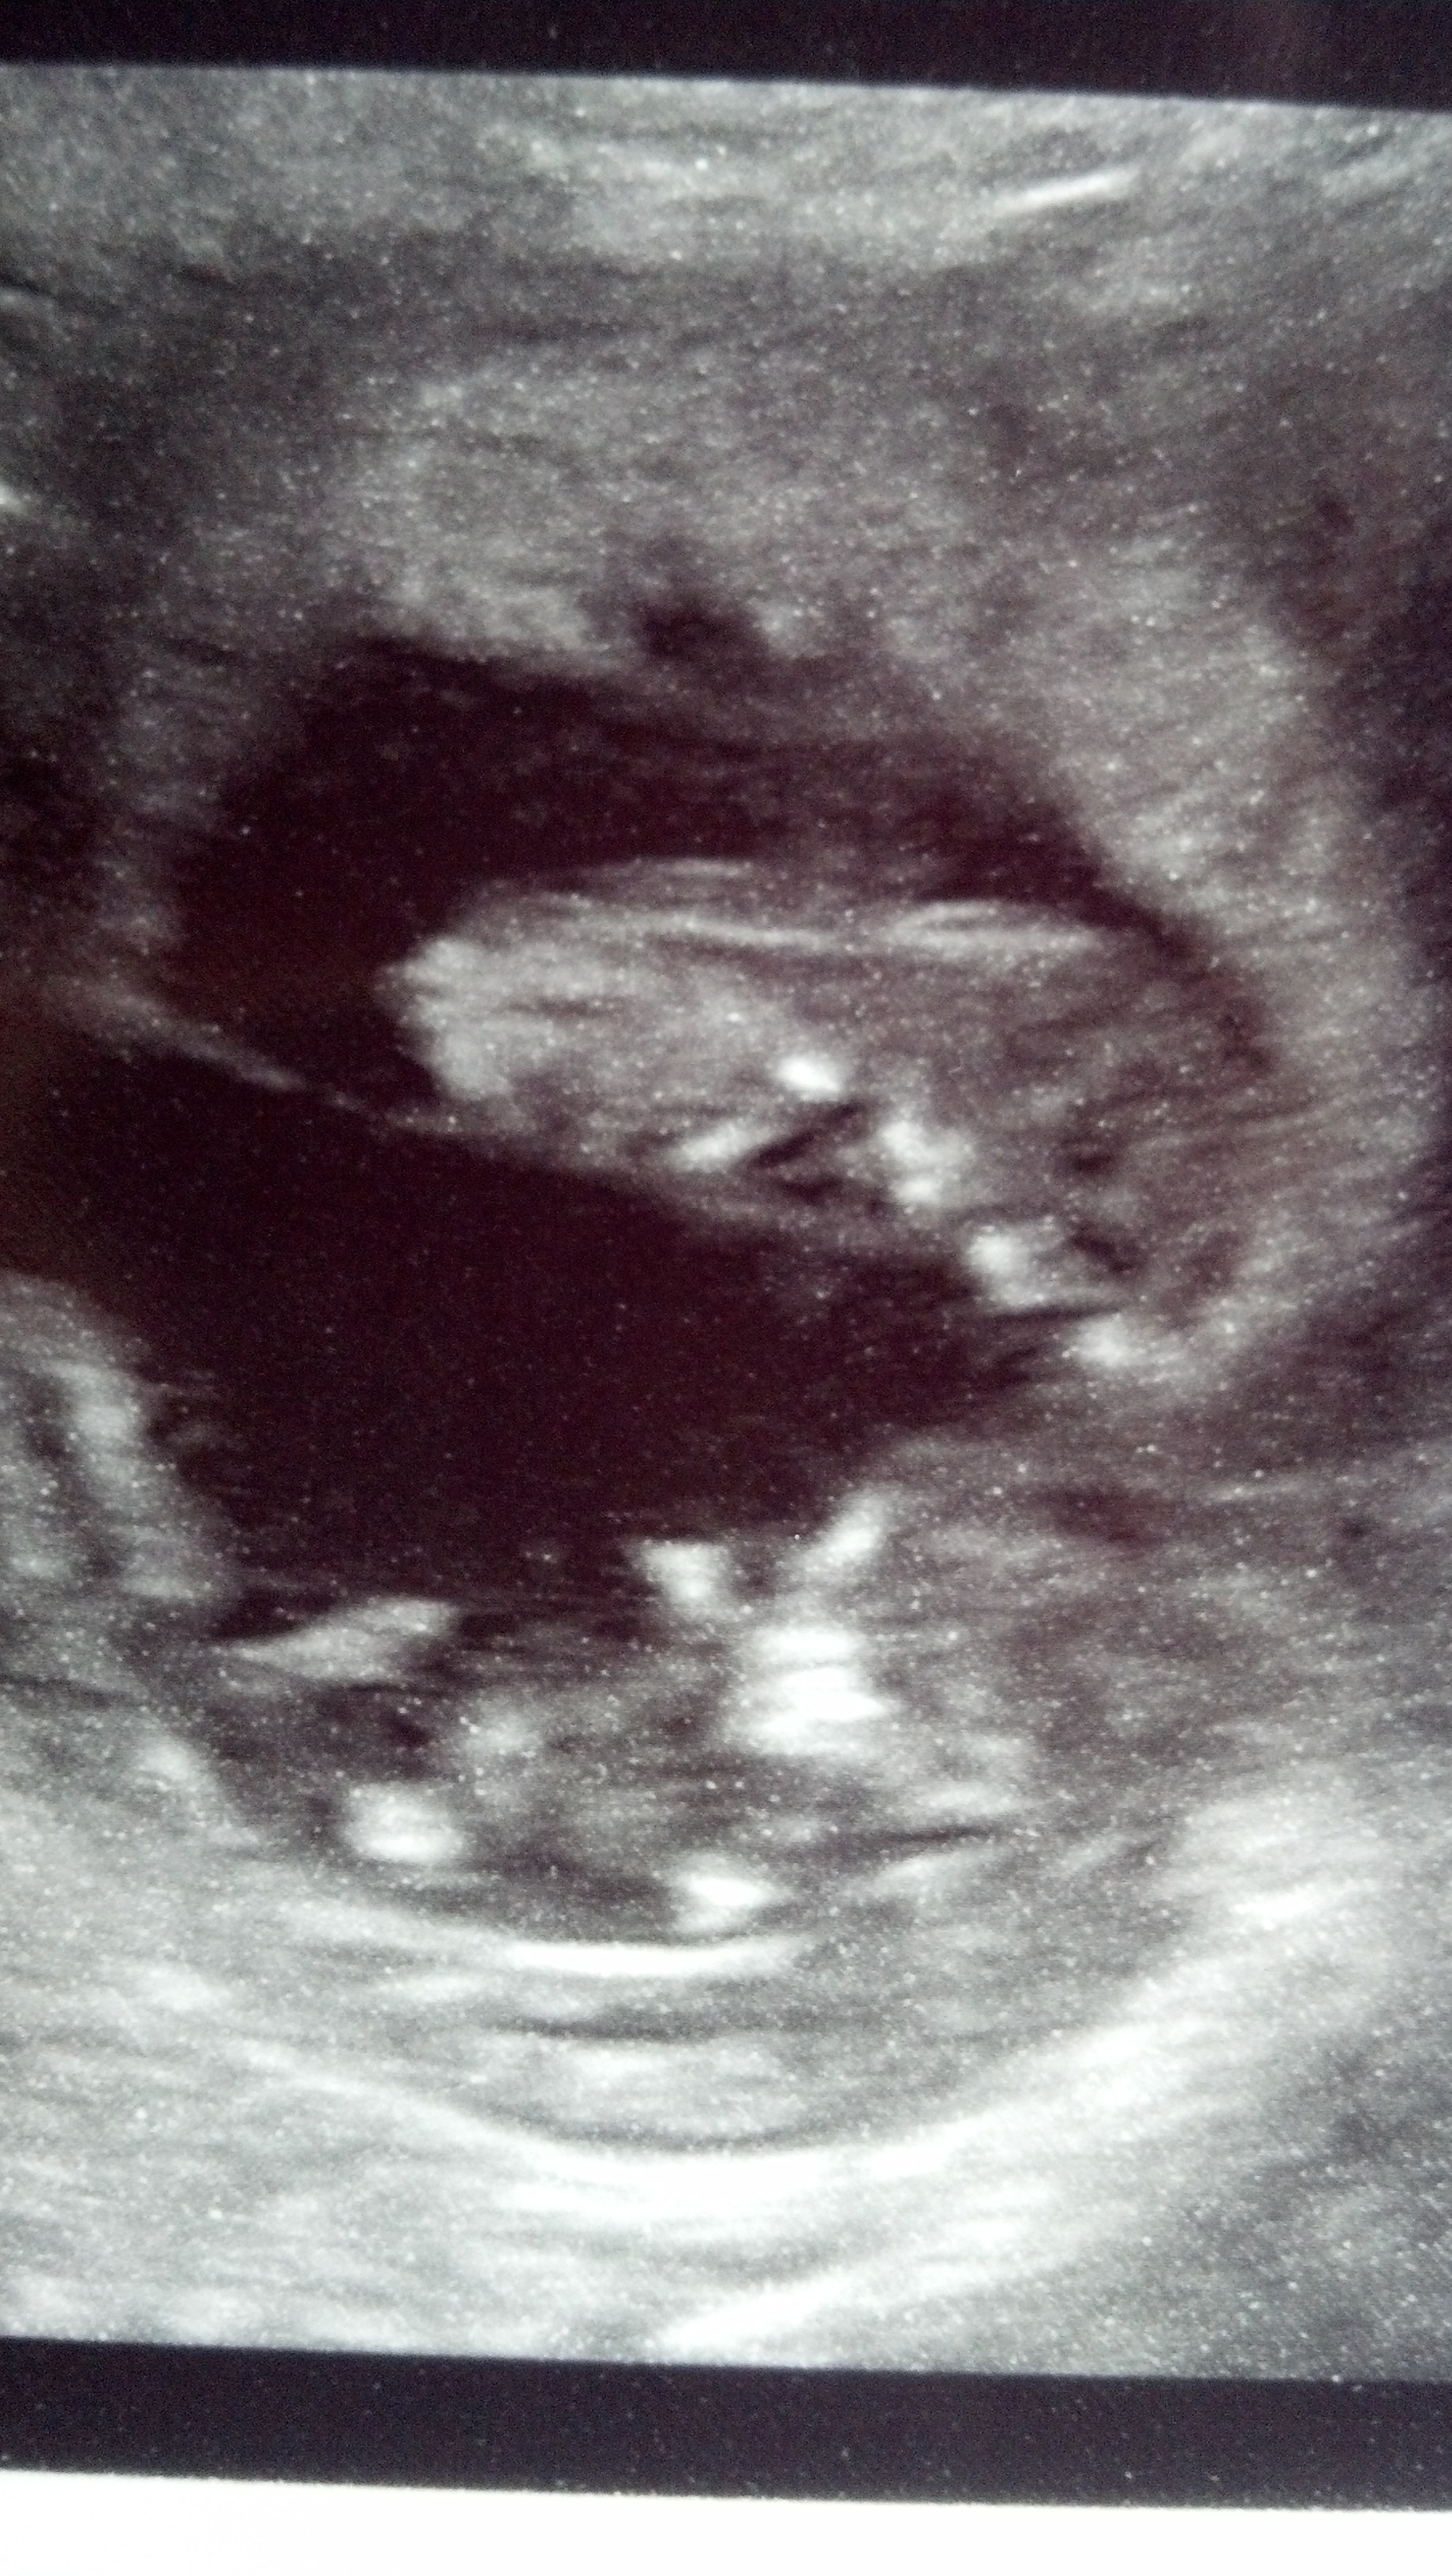

one of the last ultrasounds that we had done that both babies fit lol

IMG_20131205_145711_148.jpg